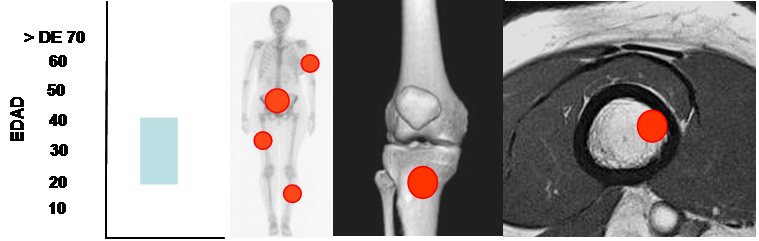

Es mas frecuente entre 20 y 40 años, con pico en la 3º década, (33, 34).

Aparece en las metáfisis de los huesos largos maduros, después que se han cerrado los núcleos de crecimiento y con predominio en la tibia. También pueden aparecer en el sacro. (13, 18, 34). (Fig 119).

Fig 119. Tumor de células gigantes.

Mayor frecuencia entre los 20 y 40 años. Predominio en los huesos largos y el sacro.

Lesión metafisiaria, de ubicación excéntrica.